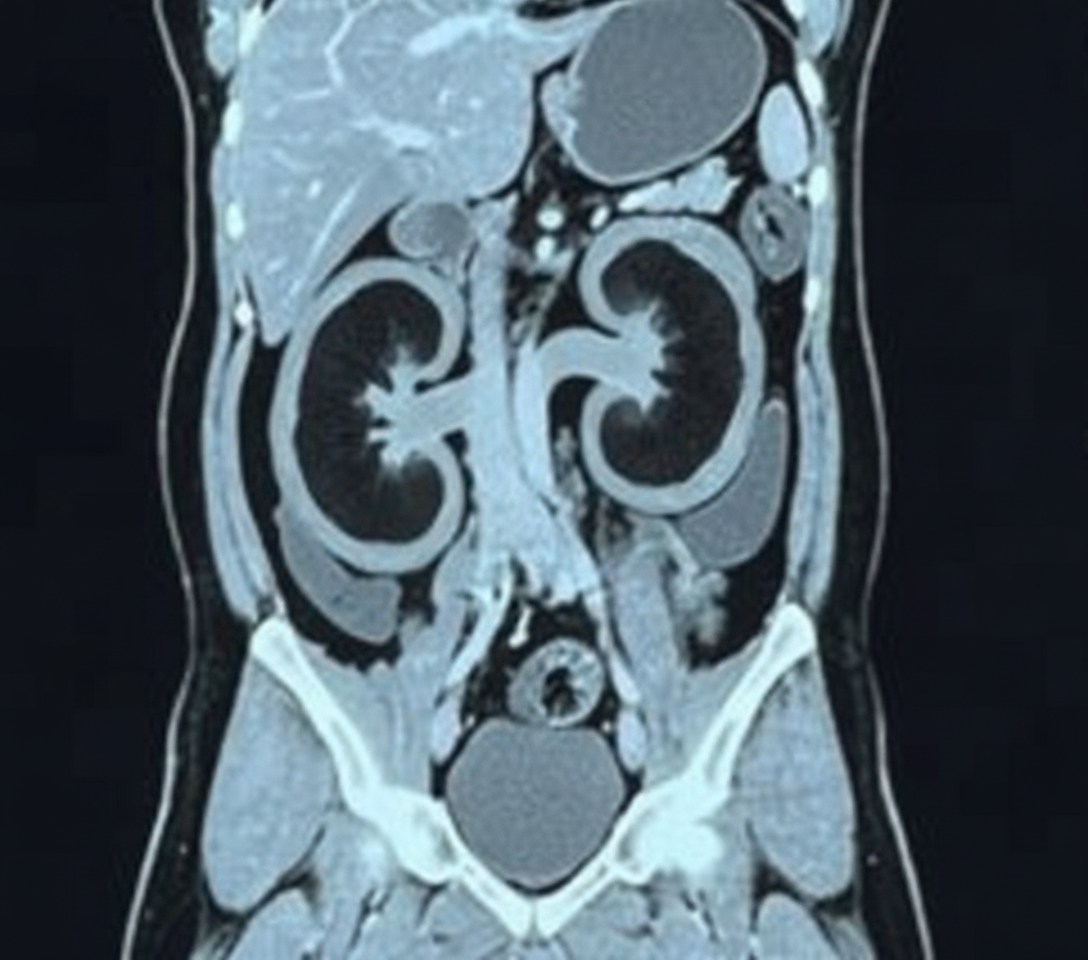

An 11-year-old girl is brought to the office by her mother due to complaint of intermittent and severe periumbilical pain for 1 day. She does not have any significant past medical history. She provides a history of a recent school trip to the suburbs. On physical examination, there is a mild tenderness around the umbilicus without any distension or discharge. There is no rebound tenderness. Bowel sounds are normal. An abdominal imaging shows enlarged mesenteric lymph nodes, and she is diagnosed with mesenteric lymphadenitis. However, incidentally, a mass of tissue was seen joining the inferior pole of both kidneys as shown in the image. Which of the following best describes this renal anomaly?